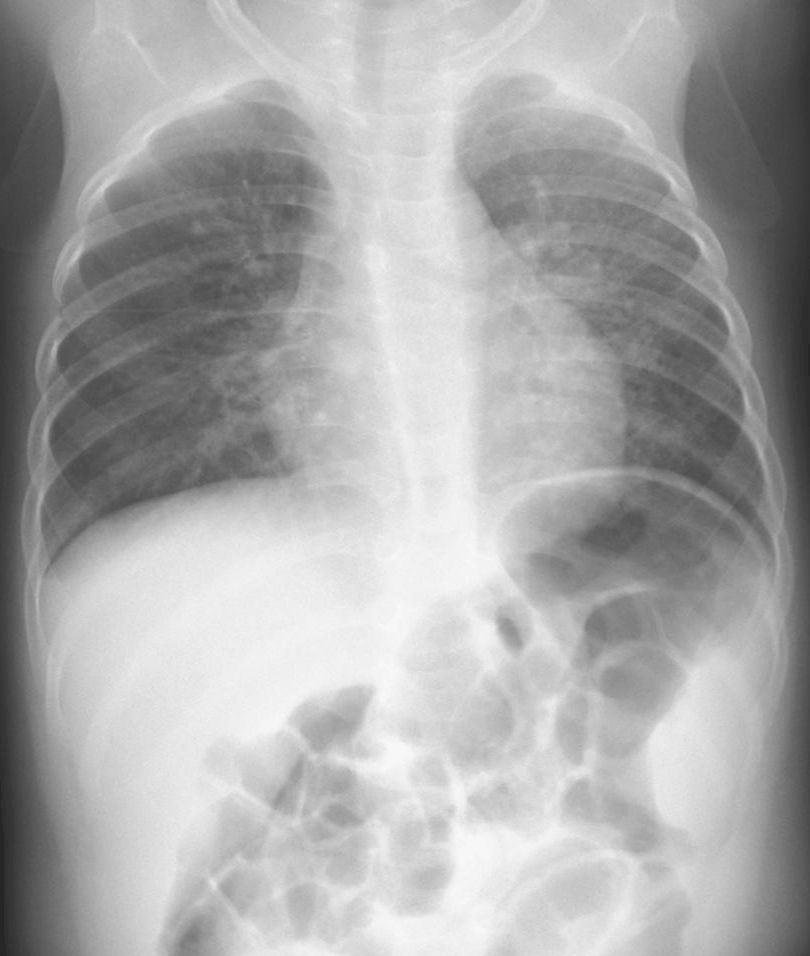

RSウイルス肺炎1歳